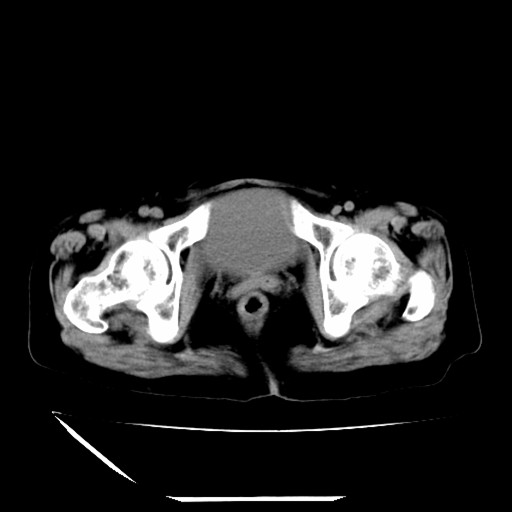

标题: CT16840:女-63岁,下腹部疼痛,

补充资料:血象是13.5,临床拟诊阑尾炎

本人诊断是右肾周围炎,阑尾炎,盆腔少许积液!

诊断右肾周围炎是因为我图像没有发完,诊断阑尾炎是因为相当于阑尾区连续两个层面可以看到增粗的阑尾显影。

道格拉斯窝内少量积液。